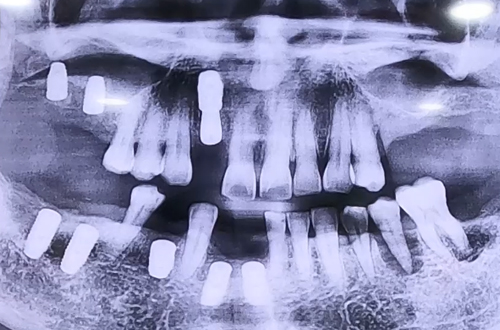

AFTER

특히 앞니는 엑스레이로 보았을 때 잇몸뼈가 상당히 얇아진 상태였기 때문에 임플란트 수술을

진행하면서 필요 시 뼈이식을 진행하기로 하여, 확인 후 뼈이식 임플란트를 시행한 케이스입니다.

오른쪽을 먼저 진행하였고 추후 왼쪽도 진행할 예정으로, 임플란트가 전반적으로 진행되면

다시금 진료일지를 통해 전달 드리도록 하겠습니다. ^^